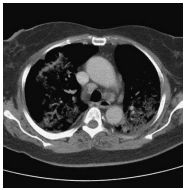

3. This 72-year-old diabetic man was taken to ER for productive cough for 10 days, and rapid progressive dyspnea for 2 days. He also had fever and chill for a week.